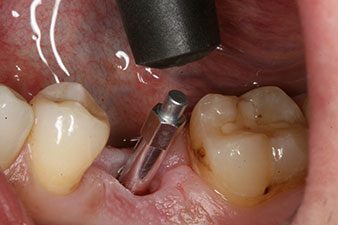

Fig. 1 : Situation clinique initiale après cicatrisation de l’alvéole où se trouvait la dent 36. La base osseuse est large et la gencive kératinisée suffisante.

Un patient de 28 ans ayant des antécédents de tabagisme important a dû se faire extraire la dent 36 à la suite d’une parodontite apicale récidivante.

Vu que les dents voisines étaient globalement intactes, la seule solution pour remplacer la dent manquante était de poser un implant.

Implant

Fig. 3 : Après préparation à l'aide du moteur d’implantologie Implantmed, un implant (4 mm de diamètre, 12 mm de long) a été vissé à l’aide du moteur avec un couple de 43 Ncm.

L’implant a été posé comme prévu après élimination complète du tissu de granulation (blueSky, bredent).

Le couple utilisé pour la pose guidée était de 43 Ncm.